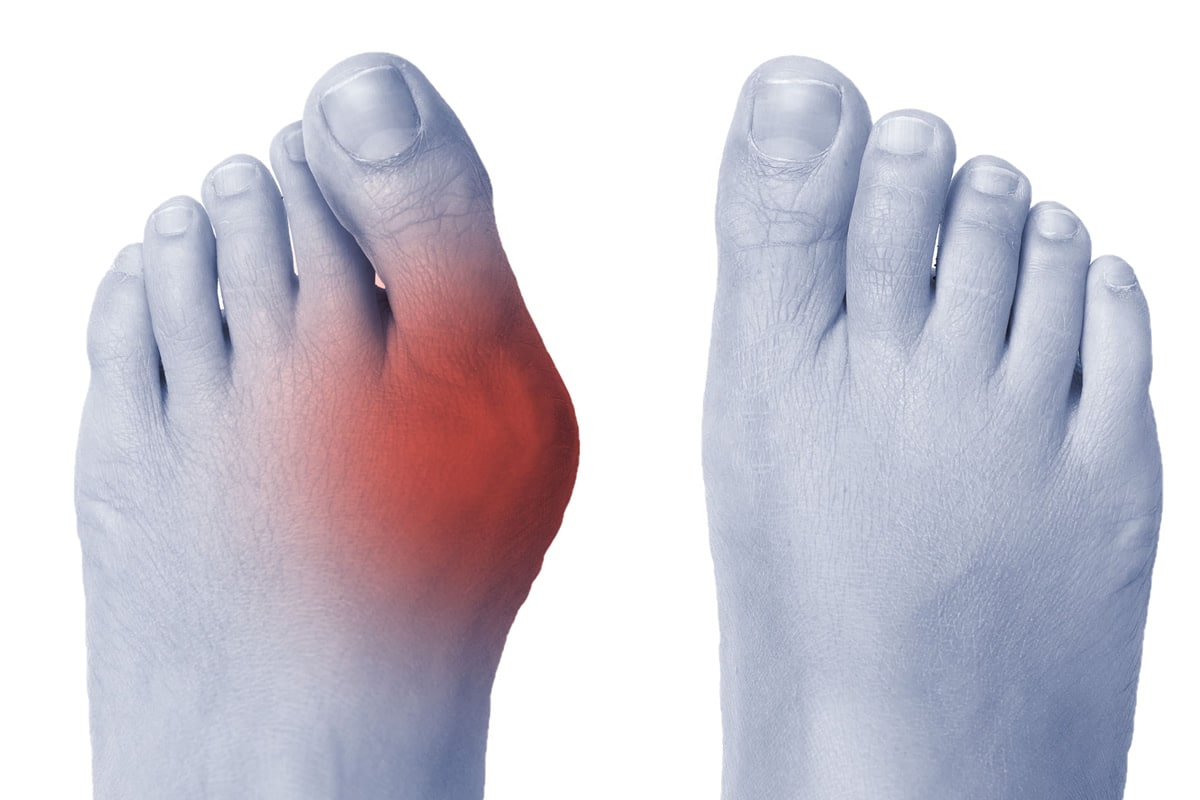

HALLUX VALGUS – JUANETE

El juanete, es el crecimiento irregular del hueso correspondiente al primer metatarsiano, que produce una desviación del primer dedo. En ocasiones, cursa con gran inflamación, provocando dolores en la zona y una mayor desviación del primer dedo. Este puede elevarse sobre el segundo y, secundariamente, provocar dolor en la planta del pie.